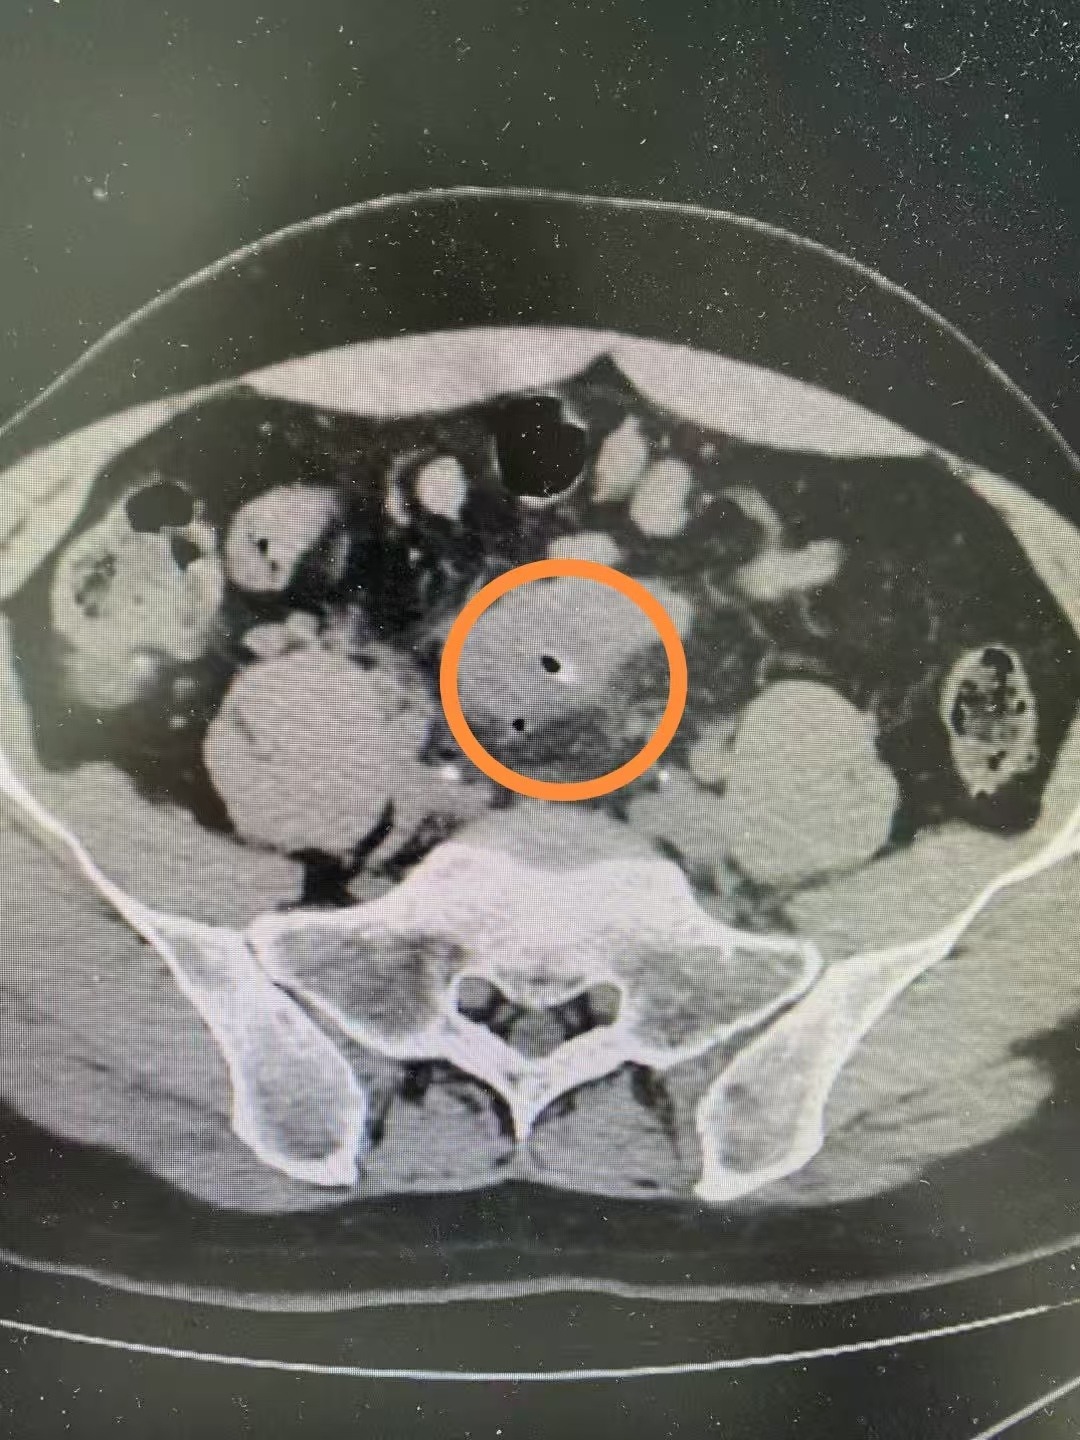

CT结果出来后,何医生发现枣核竟像钉子一样扎穿了肠子,情况十分危急。何医生马上向上级医师汇报,并请胃肠肛肠外科罗兵主治医师会诊。罗兵主治医师发现李奶奶下腹部压痛、反跳疼痛明显,且抽血提示白细胞升高明显,遂立即请示胃肠肛肠外科邱磊主任和魏君副主任医师。

无独有偶,同月,佛山市第二人民医院还接诊了一位肚痛到满地打滚的中年大叔。经腹部CT检查提示乙状结肠异物穿孔,有生命危险。邱磊主任及魏君副主任医师查看病情及结果后,当即为患者行急症手术探查,成功取出异物,也是一枚枣核。